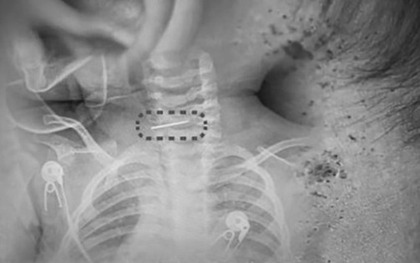

Bé trai bị sốt và co giật, bác sĩ phát hiện ra điều đáng sợ

Tiếp nhận bệnh nhi trong tình trạng sốt cao, các bác sĩ phát hiện bé có nhiều vết kim đâm khắp cơ thể. Ngoài ra còn có một cây kim khâu giày gãy đôi, mắc kẹt sâu trong đốt sống cổ.